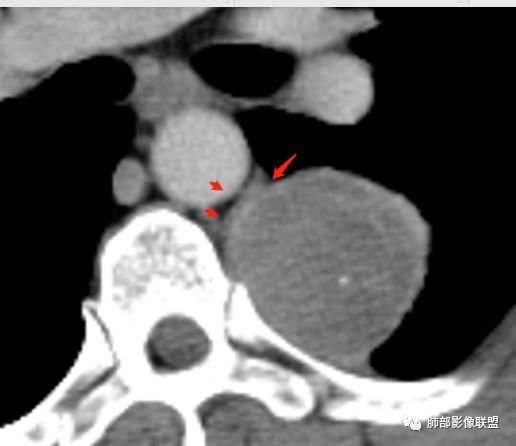

4.可疑肋间动脉病供血,提示肿块来自后纵隔的可能性。

5.相邻椎间孔未见扩大,也未见块影延入椎管,易起自于神经根的鞘瘤似乎找不到相关支持点。

6.未提供矢状位骨窗图像,如在肋骨内下缘观察到压迹有助于肋间神经的鞘瘤的判断,这是因为二者之间密切的毗邻关系。

7.静脉期轻度强化,注意不是环形强化,亦未显示明确的“AB区”,神经鞘瘤与副节瘤亦未找到支持点。

综上,病灶定位胸壁或后纵隔,就发病率而言,神经源性可能性较大。